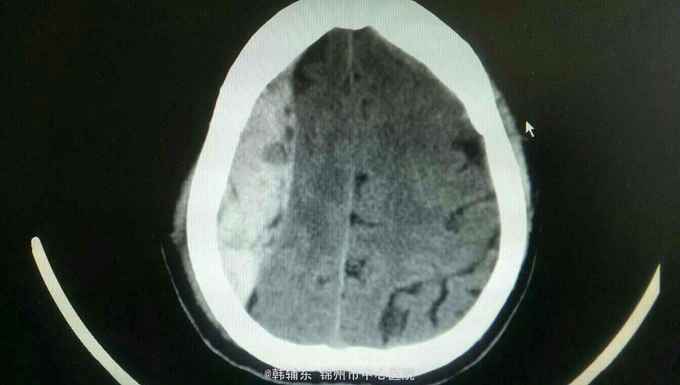

诊断:脑疝 急性硬膜外血肿 脑挫裂伤 颅骨骨折 入院后完善术前准备,急诊行去骨瓣硬膜外血肿清除术。术中见骨折线,清除血肿,悬吊硬膜。术后复查ct提示对侧脑挫裂伤增大,伴水肿,暂不需要手术。降颅压治疗,密切观察病情变化。

患者术后意识朦胧,瞳孔恢复正常。硬膜外血肿为神经外科常见疾病,及时手术效果很好,尽快在脑疝前手术可挽救生命并保留骨瓣。如果血肿量大,脑疝时间较长,脑组织水肿,应弃去骨瓣,敞开硬膜以缓解压力。